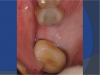

Based on this information, a CAD/CAM 3D surgical guide was printed (Figure 8). Fabrication of a full-arch surgical guide is highly recommended to provide maximum stability and retention during the surgery. The guide was tried in the patient’s mouth (Figure 9), and proper seating was confirmed.

A supracrestal subperiosteal flap extending from the bicuspid to the second molar was reflected, exposing the alveolar ridge. The implant was placed and allowed to heal, and the patient returned for the restorative phase of treatment. Because the implant placement was slightly to the facial, a decision was made to retain the restoration with cement. A custom platform-switched abutment was fabricated with the finish line at the gingival margin to facilitate cement removal.

Fig 8. 3D surgical guide.

Figure 8

Fig 9. Guide tried in patient’s mouth.

Figure 9